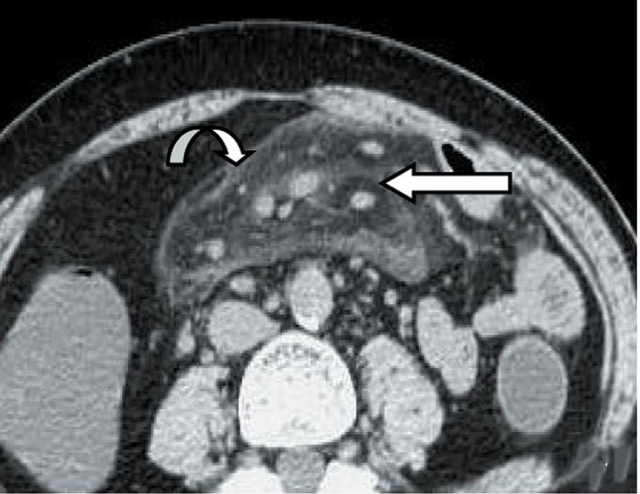

(1)急性部位肠系膜脂膜肚子炎:急性肠系膜脂膜炎病灶范围较大,小腹变大是怎么回事,CT平扫可见局限性脂肪密度增高影或肿块影(位于系膜区,大部分小肠系膜,也可以是结肠系膜),病灶包绕但不左边侵犯肠系膜血管,可形成“假肿瘤包膜征”、“脂肪晕环征”;而急性肠脂垂炎呈与肠管相连、范围较小征兆的局灶性病灶,一般不累及小肠系膜。

上图是非常介绍典型的肠系膜脂膜炎CT图像。CT平扫病灶位于小肠鼓像系膜,推挤周围肠管,密度明显高于腹膜后正常脂肪密度,呈脂肪性包块,包绕肠系膜血管,弯箭所示包块边缘,直箭所示“小结节”及其周围“脂环征”。